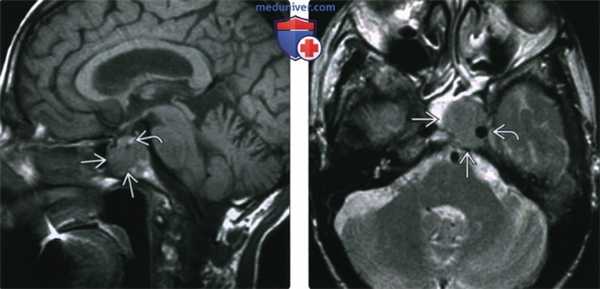

(Слева) При МРТ Т1ВИ в сагиттальной проекции у мужчины 82 лет с жалобами на головные боли и патологическими изменениями придаточных пазух при КТ определяется солитарная инфильтративная плазмоцитома тела клиновидной кости, пролабирующая вперед в клиновидную пазуху. Новообразование отлично от нижнего края гипофиза.

(Справа) При МРТ Т2ВИ в аксиальной проекции определяется слегка гиперинтенсивное по сравнению с головным мозгом объемное образование, распространяющееся в клиновидную пазуху и латеральнее в левый кавернозный синус и окружающее левую внутреннюю сонную артерию.

(Слева) При МРТ Т1ВИ FS с КУ определяется солидное равномерно контрастируемое (новообразование) ва; признаки некроза или «пустоты потока» отсутствуют. Обратите внимание, что передний край объемного образования легко отличим от контрастной слизистой носоглотки.

(Справа) При МРТ Т1ВИ FS с КУ наблюдается контрастирование плазмоцитомы, затрудняющее дифференцировку опухоли от контрастной ткани гипофиза. Эта плазмоцитома симулирует инвазивную макроаденому.